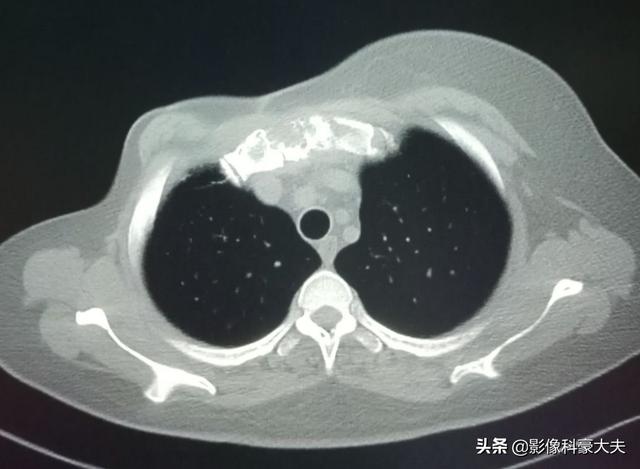

私たちの診療科にはいつもこのような患者さんが来ますが、毎回最初に出てくる症状は、転移部位の骨の痛みです。たとえば先週、『先生、背中が痛くて夜も眠れないし、夜中に痛みで目が覚めることがよくあります』と訴えてきた患者を診ました。この患者は54歳の中年男性で、普段からタバコと酒が好きな人だった。簡単に病状を聞いてみたが、腰痛が唯一の症状だった!彼自身に基礎疾患はなく、家族にもがん患者はいなかった。そこで、私は彼のためにその部位のCT検査を手配した。結果は予想通り、腰椎の骨破壊で、骨転移がんと考えられた。患者さんが男性であることを考えると、肺がんや前立腺がん自身の腸の腫瘍はこの部位に転移しやすいので、胸部、腹部、骨盤のCTを手配し、その結果、右側の肺に影があり、肺がんと考えられた!翌日、呼吸器科に移され、その後、CTガイド下肺穿刺を受け、病理検査の結果、肺腺癌と診断された。